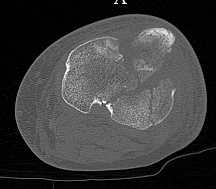

Серия КТ сканов в аппарате

Голень-41-С3.1 - полный внутрисуставной и метафизарный оскольчатый перелом с доминантным повреждением наружного мыщелка, с импрессией центральной части плато. Первичная тактика полный респект по АО и ОТА. на фоне лигаметотаксиса выполнено КТ, которое четко детализирует повреждение и определяет дальнейшую тактику.

Основная проблема не бугристость, а внутрисуставное повреждение латерального мыщелка с импрессией центральной части. С большей вероятностью, есть паракапсуллярное продольное повреждение наружного мениска.